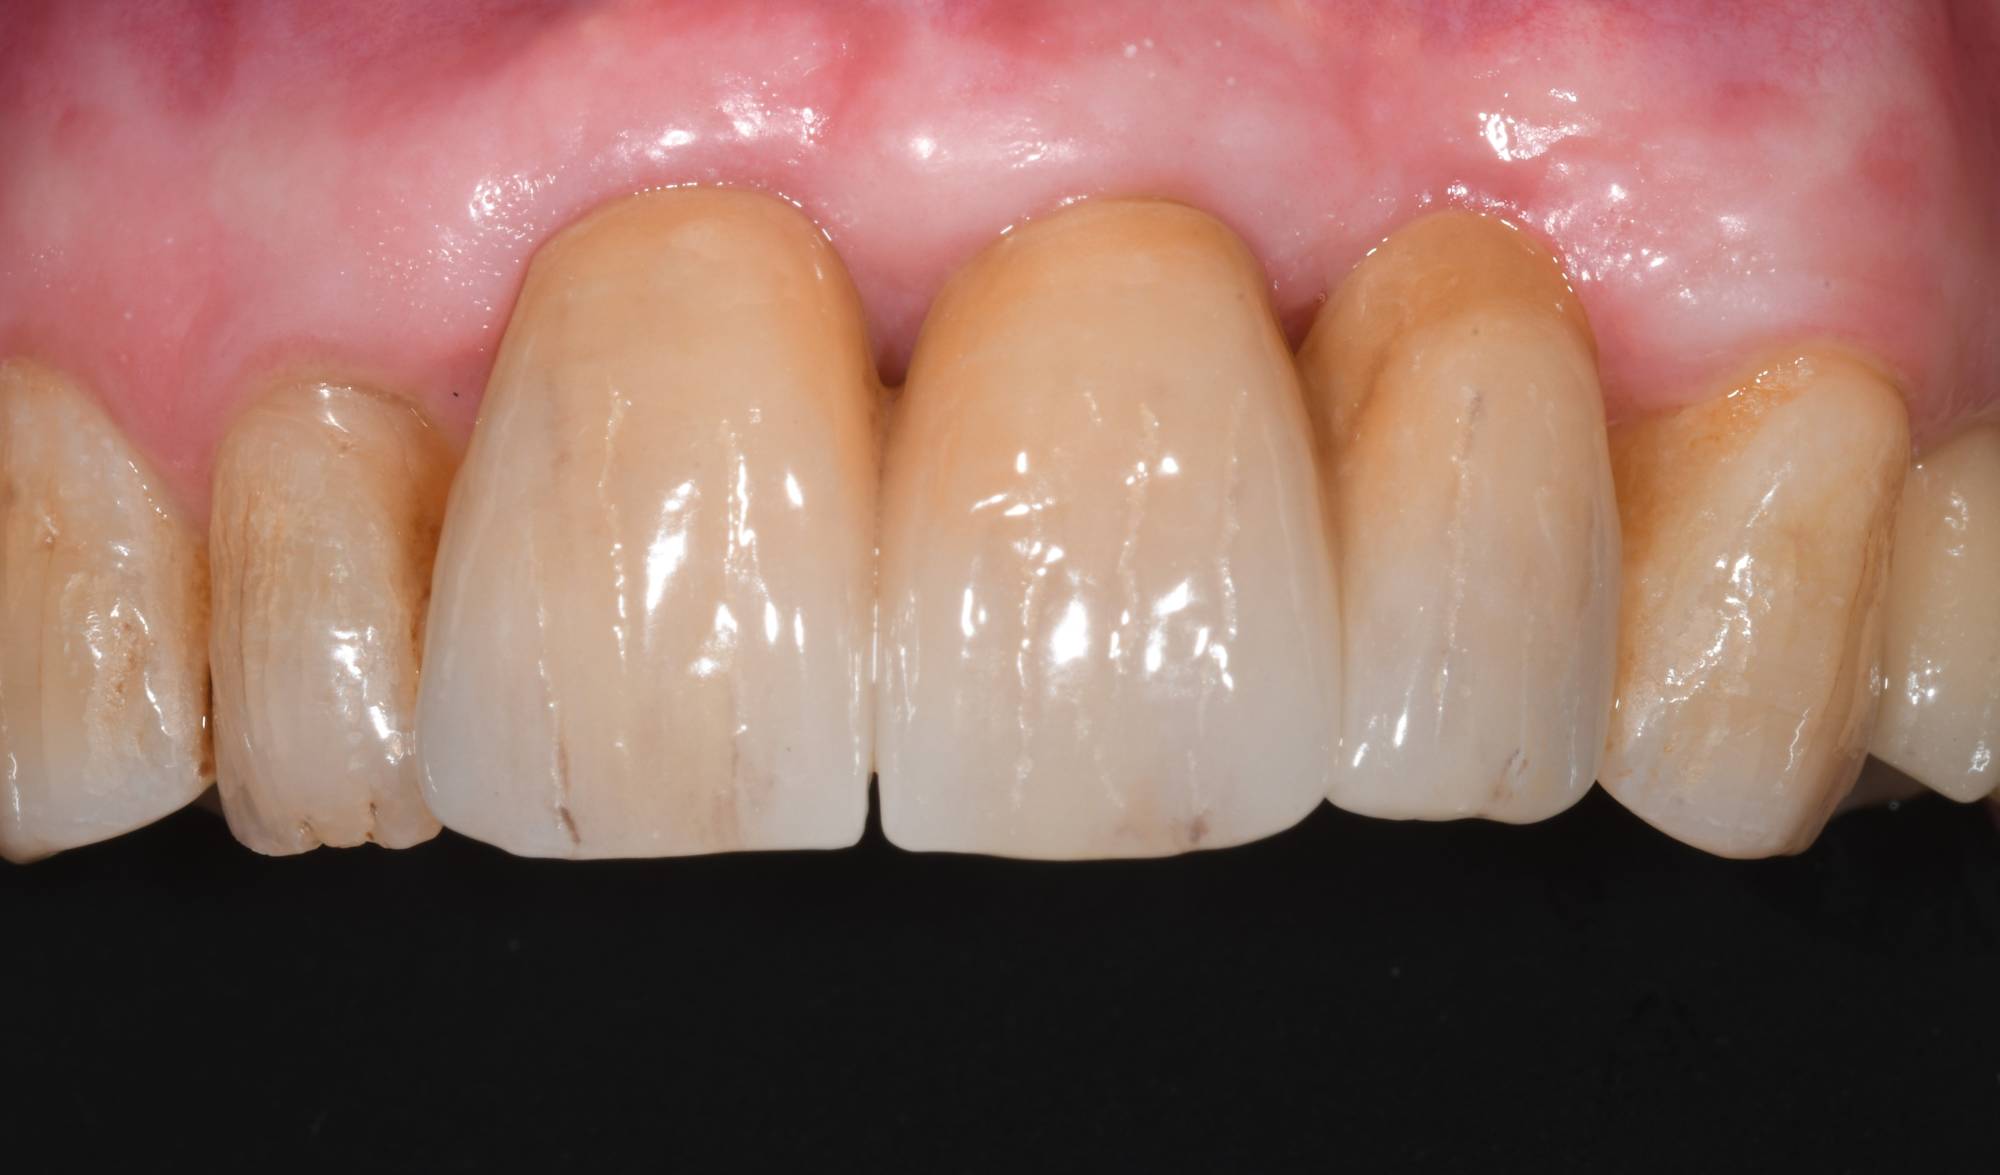

Tutto a posto in questa foto? Premesso che si tratta di una signora anziana, i denti si presentano scuri e “vissuti”, con imperfezioni tipiche di chi quei denti li ha usati a lungo. Le gengive però sono perfette e assolutamente non infiammate.

E se ti dicessi che alcuni di questi denti sono artificiali, addirittura due sono degli impianti? Su quale scommetteresti? Ti sei mai fatto dei problemi a mangiare o sorridere? Alle volte un vecchio ponte sugli incisivi può iniziare a muoversi perché i pilatri sottostanti sono cariati o fratturati. Questo disagio può toglierti la possibilità di masticare normalmente e la voglia di ridere, vista la paura di perderli da un momenti all’alto.